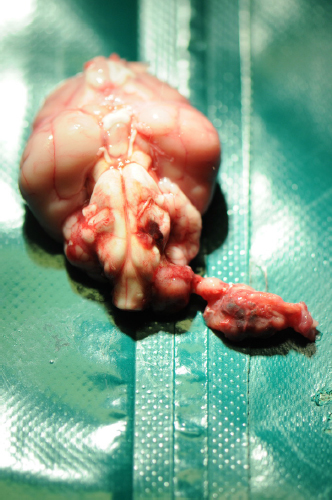

Histological examination described a nonencapsulated, moderately cellular, rather loose, proliferation of cuboidal to columnar epithelium breaching through chunks of an otherwise normal appearing dura mater and invading some cranial nerves. Cells were arranged in papillae, large cystic lacunae with low amount of faintly eosinophilic amorphous material, or glandular architecture, depending on the region considered (Fig. 3).

These cells were supported by a moderate amount of moderately vascularized stroma. Cells presented with moderate anisocytosis and mild anisokaryosis with variations in between cuboidal and columnar ciliated epithelium, mildly increased nucleus/cytoplasm ratio, and nonpolarized nuclei. There were 15 mitoses in 5 high-power fields. Immunohistochemistry for pancytokeratin displayed diffuse immunoreactivity of the proliferating cells (Fig. 4), also showing high ki67 positivity, while neuron-specific enolase and glial fibrillary acidic protein were negative. Sections of the cerebellum and brainstem revealed moderate, focal, impingement of the parenchyma with very mild extension of the proliferating cells into the ventral left side of the medulla oblongata. Very mild perilesional edema, mild multifocal microglial activation, and very mild diffuse astrocytosis and astrogliosis were detected at this level. Eosinophilic neuronal necrosis was also occasionally observed. Similar reactive changes of the neuroparenchyma were encountered along the ventral paramedian lobule and paraflocculus with no clear evidence of invasion by proliferating cells. Location, morphologic features, and immunohistochemical labeling were consistent with a diagnosis of ELST .

Fig. 3. ELST. Neoplastic cells grow forming papillary projections lined by one to two layers of polygonal cells and supported by a delicate fibrovascular stroma (H&E stain; scale bar=100 µm).